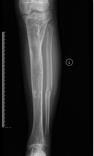

桡骨陈旧性骨折骨不连、畸形

先天性胫骨假关节

肢体短缩延长术,延长9厘米